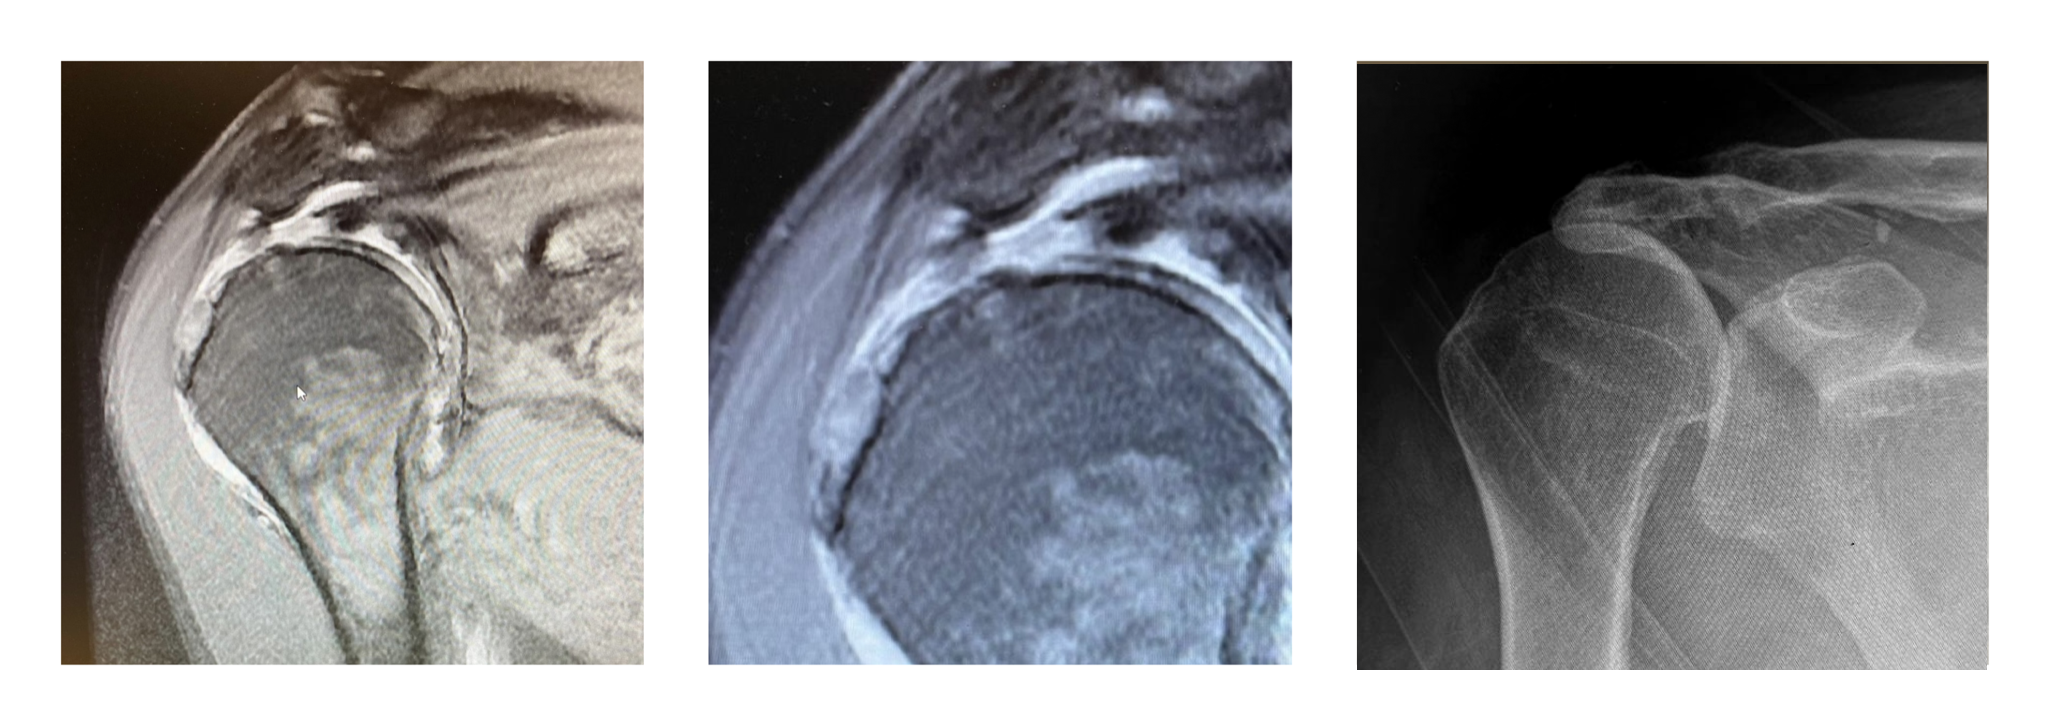

L’intervento di protesi di spalla si rende necessario prevalentemente in presenza di lesioni massive e irreparabili della cuffia dei rotatori, associate ad artropatia da cuffia (cuff tear arthropathy). Questa condizione si sviluppa quando una rottura cronica e di grandi dimensioni della cuffia porta a un’alterazione della biomeccanica dell’articolazione gleno-omerale, causando la progressiva degenerazione della cartilagine articolare.

In questi scenari, il trattamento conservativo (fisioterapia, infiltrazioni) offre generalmente un sollievo sintomatico limitato e non risolve il problema meccanico sottostante. Una retrazione eccessiva, una scarsa qualità del tendine o un’atrofia muscolare avanzata possono rendere impossibile una riparazione chirurgica diretta dei tendini.